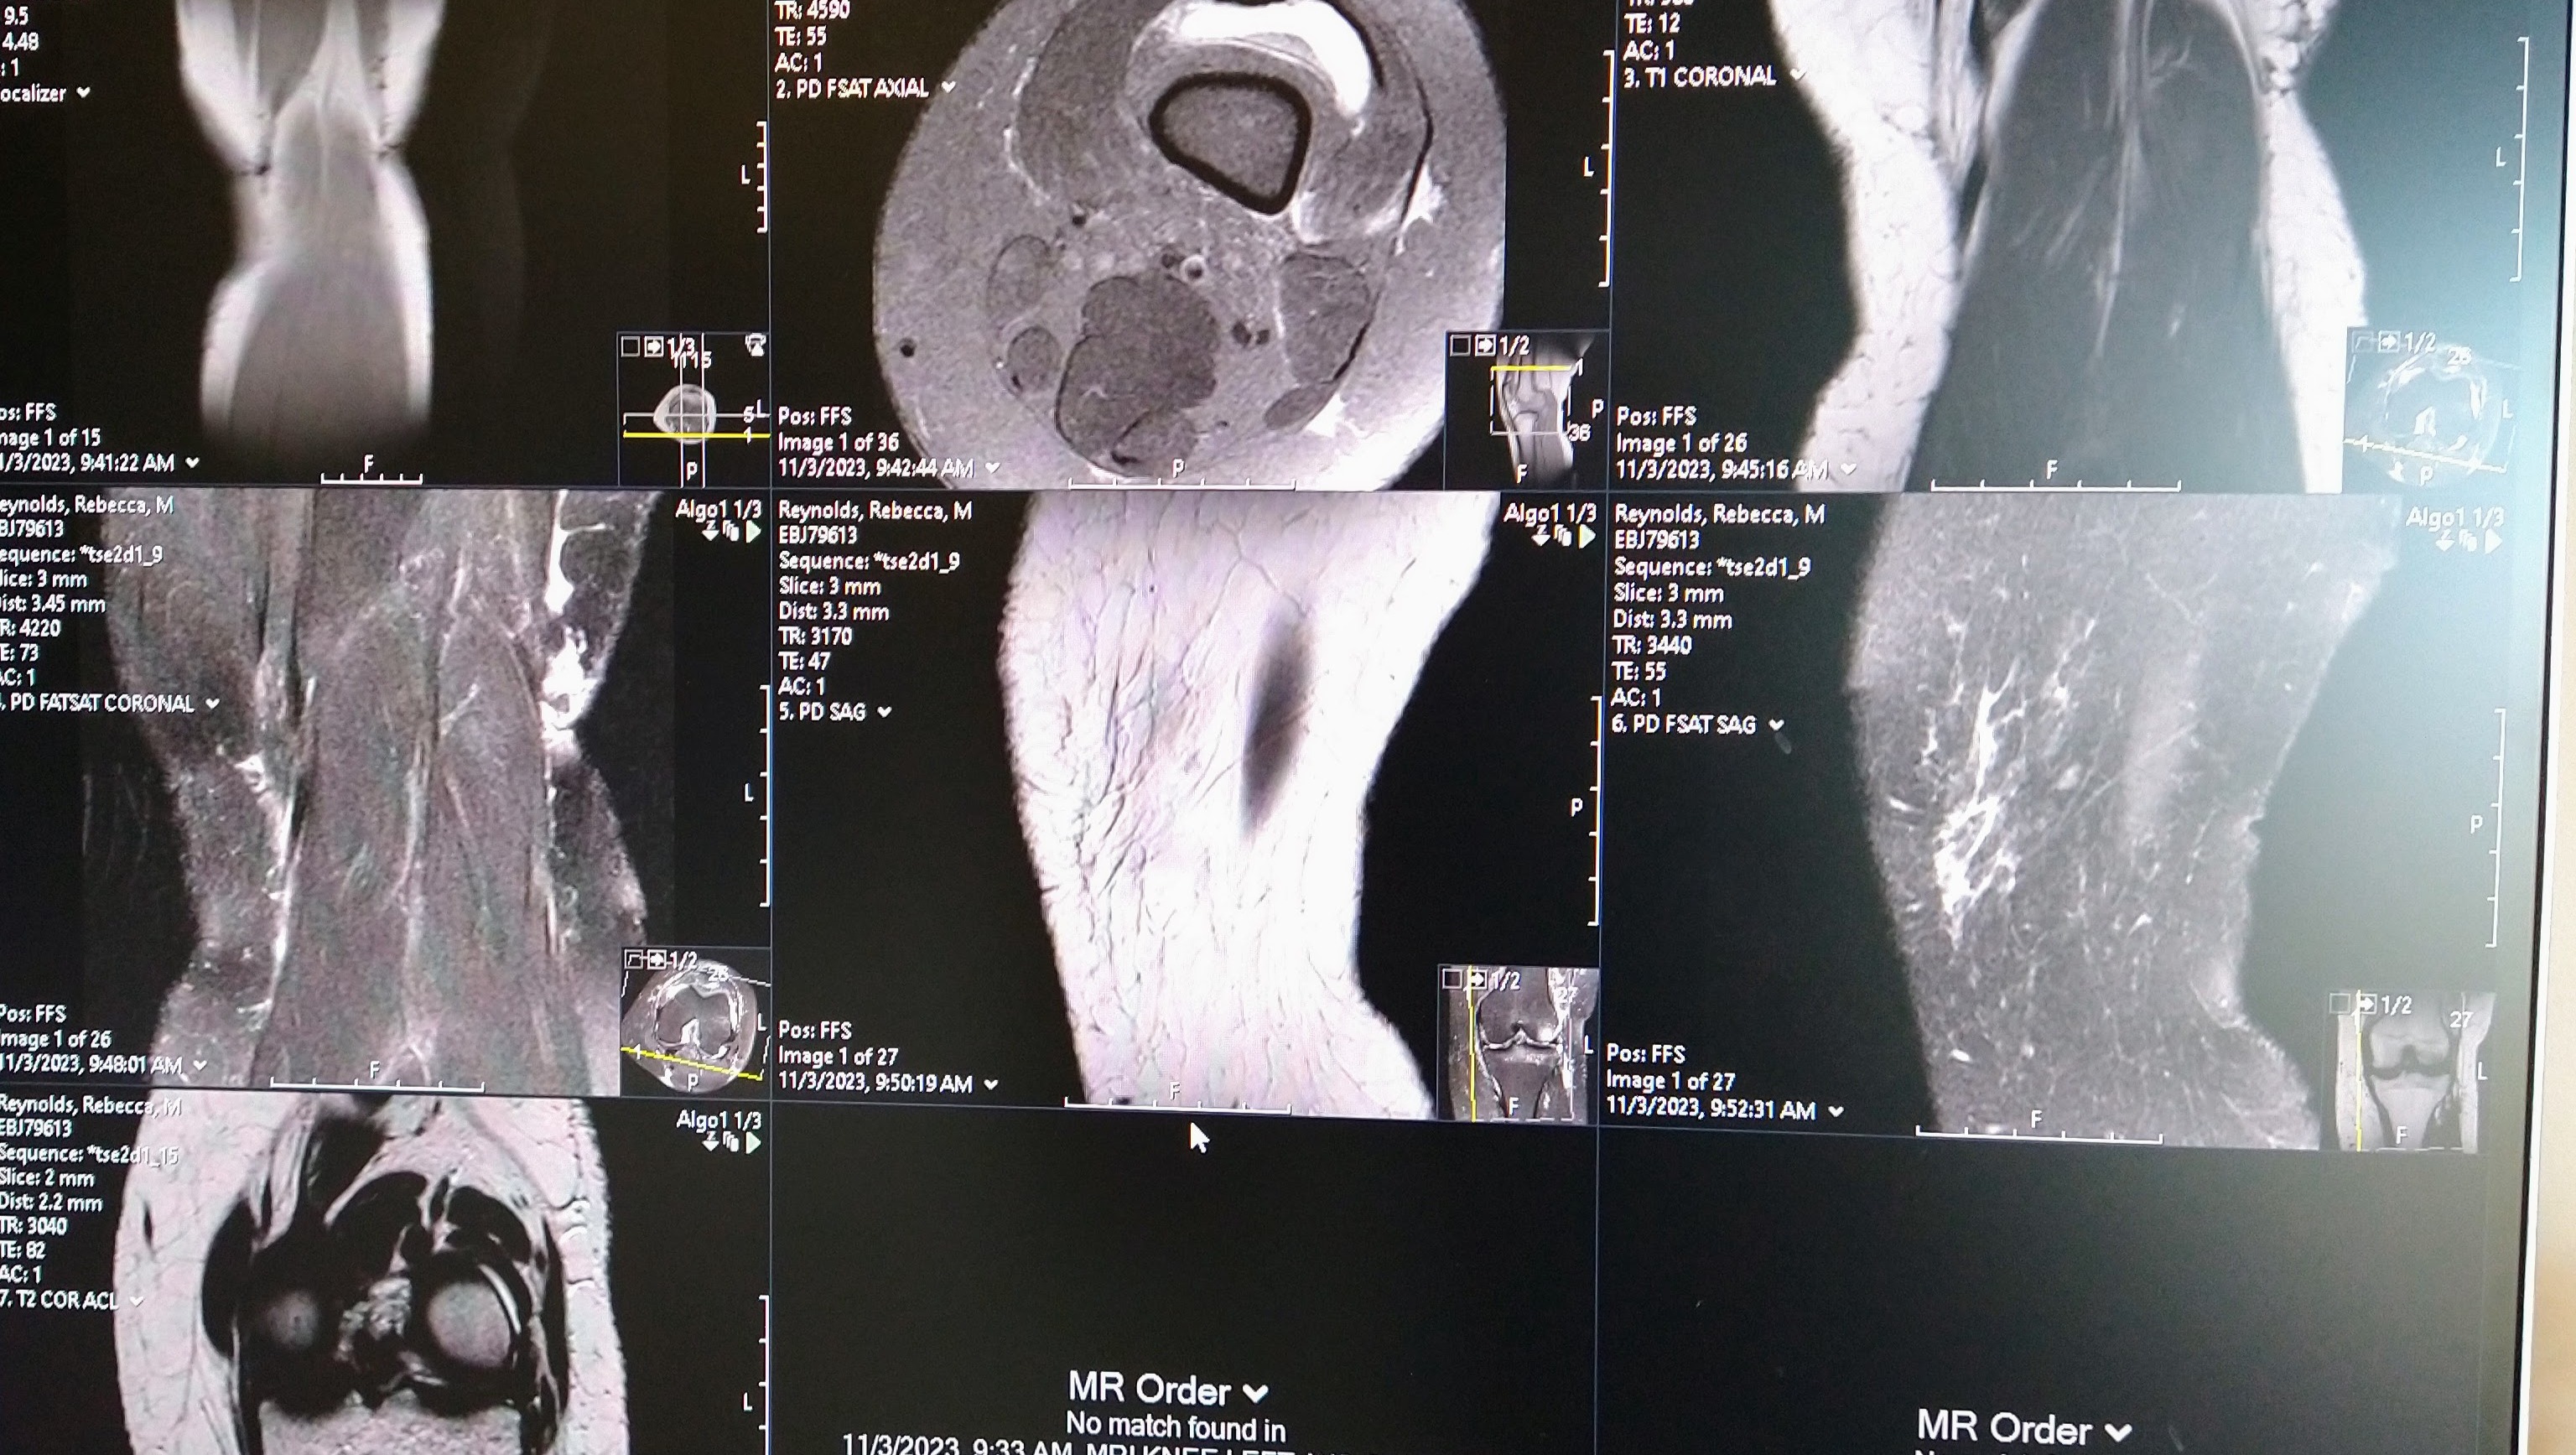

My mom has a good heart, despite everything she’s been through. She found some baby kittens behind some storage trailers. She said there was rat poison back there and she didn’t want them to get hurt. She went around to get all the kittens but fell off the ledge. Now she’s hurt bad. She tore her ACL and damaged the cartilage in her knee.

Two days ago, my mom got off the phone with the doctors. They said she needs surgery immediately to fix her knee, but we need to pay $3000 before they will schedule her.